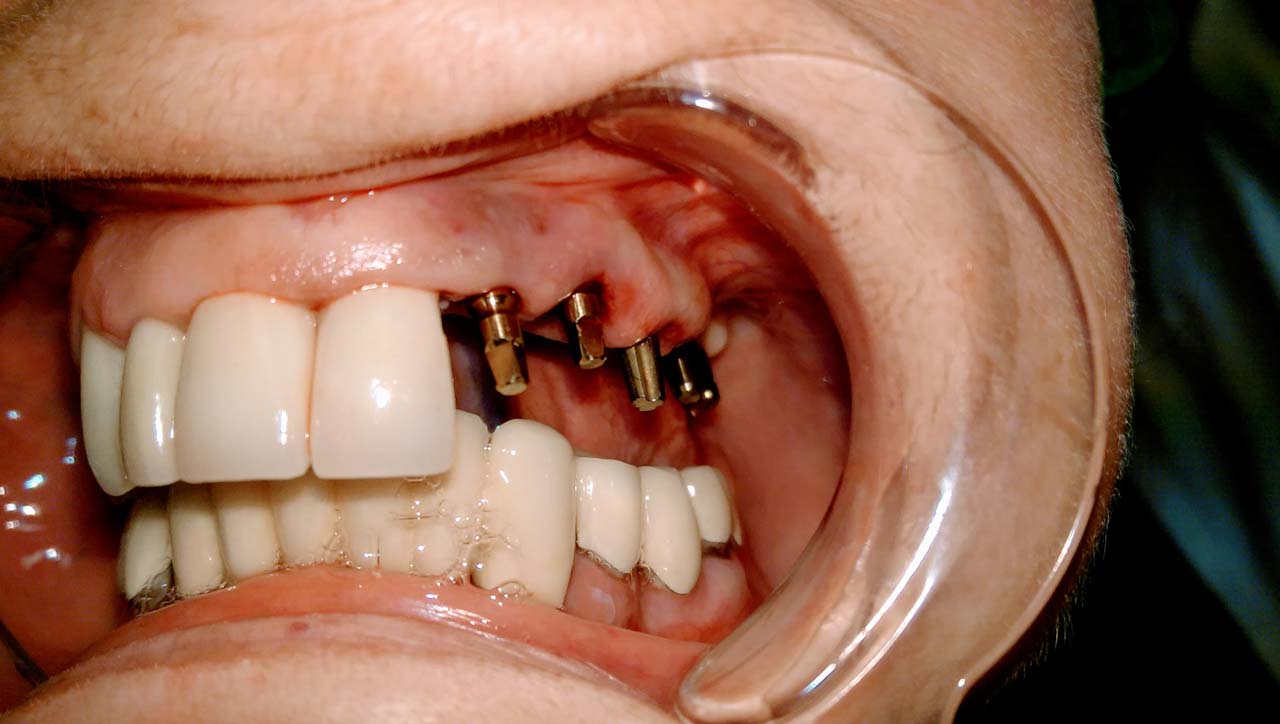

Elhanyagolt fogsor cseréje 2 nap alatt

2 nap alatt varázsoltuk ezt a szép esztétikus alsó, felső körhídat implantátumokkal megtámasztva a korábban elhanyagolt szájba. Az 1. nap 26 fogat távolítottunk el, mert annyira rossz állapotban voltak, és rögtön azonnal terhelhető IHDE svájci implantátumokat raktunk be, fentre 8, lentre 6 darabot. A sebeket összevarrtuk és intraorális szkennerrel digitális lenyomatot vettünk. 2 nap múlva pedig beragasztottuk a kész PMMA műanyag körhidakat. Dr. Kelemen Péter és a Symbion Fogtechnika munkája.